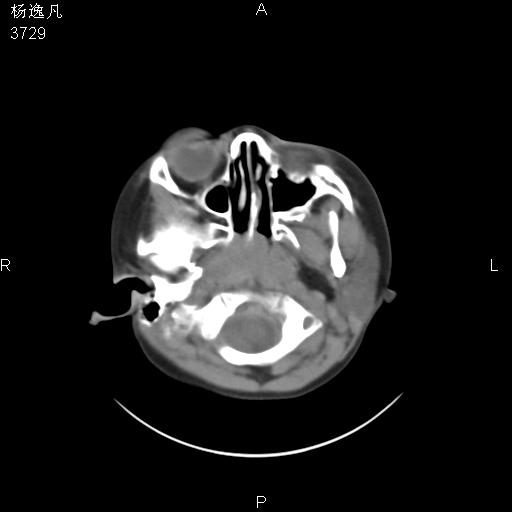

男性,5岁,面部受外伤,余无特殊

骨窗

1、右面部及颞部软组织肿胀。

2、腺样体肥大。

头颅ct平扫未见明确外伤性征象,右侧面部及颞部软组织肿胀,后鼻腔软组织影增大,增厚,鼻咽顶部变窄,考虑鼻咽腺样体增值肥厚。

双侧位置太不对称,未见明显骨折征象。